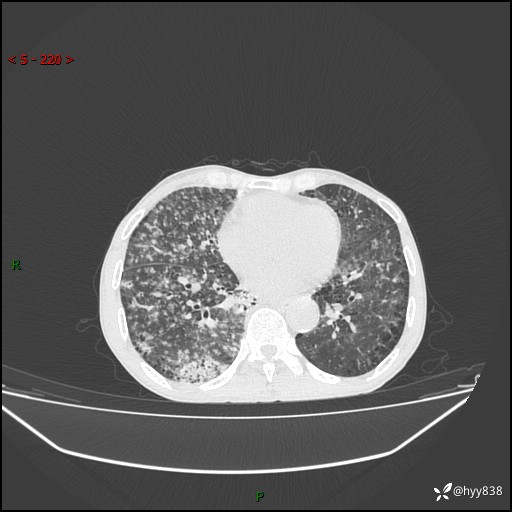

胸部CT平扫